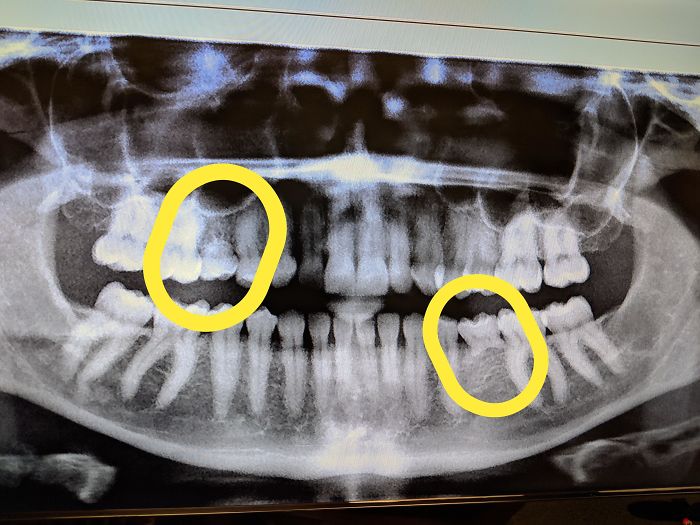

I Have A Rare Disorder Called Cleidocranial Dysotosis. Got My First Dental X-Ray Today And I Have A Lot Of Extra Teeth

I Took An X-Ray Today And They Told Me That My Wisdom Teeth Are Pretty Strange

I Have 5 Wisdom Teeth

I Went To The Dentist For Tooth Pain, I Got My X-Rays Taken And The Dental Assistant Said My Wisdom Teeth Were "Like Something Out Of A Textbook"